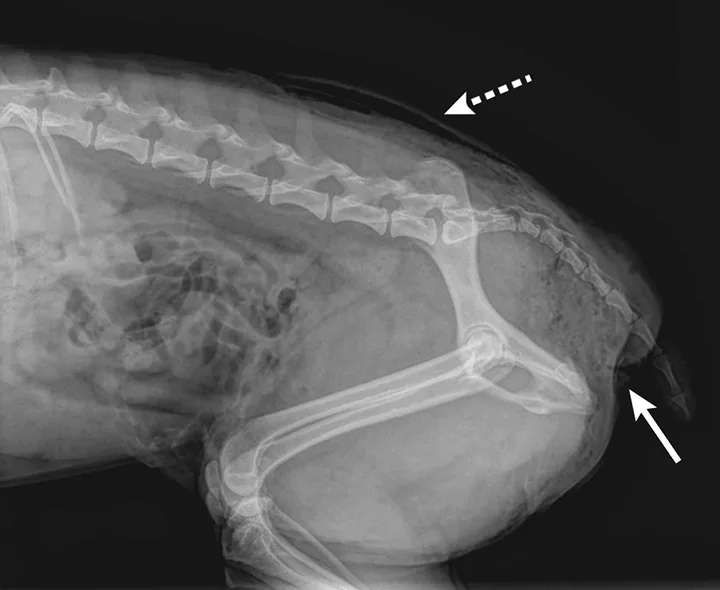

Perineal subcutaneous emphysema (solid arrow). Bites near the tail should be inspected for nerve injury and rectoanal damage. Subcutaneous emphysema can also be seen in the dorsocaudal area (dashed arrow).